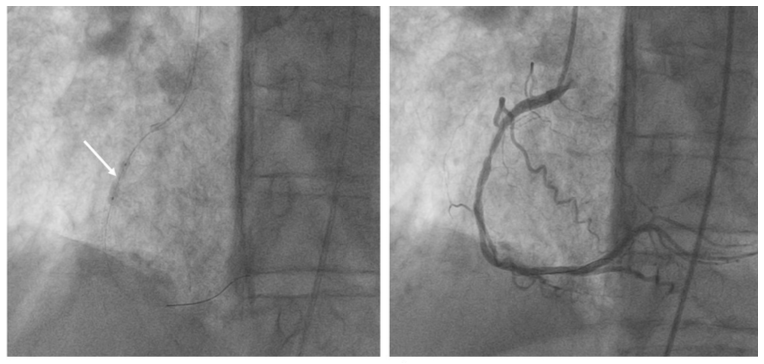

A 67-year-old male presented with non-ST-elevation myocardial infarction (STEMI). Angiography showed severe restenosis within the previously (before 2 years) implanted 2 stents (3 x 24 mm) in the right coronary artery (RCA). Severe calcification was evident angiographically (Figure 1) and after multiple dilations with noncompliant (NC) balloons, the focal underexpansion of the stent remained (Figure 2). This was confirmed by intravascular ultrasound with a minimum stent area (MSA) of 1.98 mm2 (Figure 3). A 3 x 12 mm intravascular lithotripsy (IVL) balloon was used and after the third series of 10 pulses, full expansion of the stent was observed (Figure 4). Postdilation of stenosis with NC and drug-eluting balloons was accompanied by excellent angiographical result with residual stenosis 0%, Thrombolysis in Myocardial Infarction 3 flow, and MSA of 6.4 mm2. The patient was discharged free of symptoms and remains uneventful with no complications. The case demonstrates the feasibility of IVL in acute coronary syndromes related to stent underexpansion due to severe calcification that is refractory to other conventional techniques.